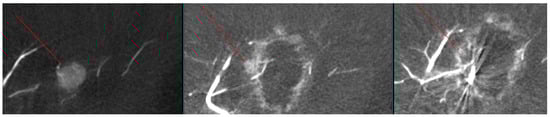

Figure 6. Images from another patient with hepatocellular carcinoma undergoing angio-CBCT-guided RFA. (Left): Pre-ablation angio-CBCT shows an enhancing mass in the left lobe (line marking). (Middle): Post-ablation angio-CBCT shows an incomplete ablation margin with hyperemia, and a small enhancing nodule attached to the margin, likely representing a residual mass (line marking). (Right): Post re-ablation angio-CBCT shows a complete ablation margin with the disappearance of the residual mass (line marking).

As shown in Figure 1, angio-CBCT allows for higher visibility of the target mass, as reflected in the ΔHU values. This can be visually confirmed in several cases. Representative cases in Figure 2 and Figure 3 demonstrate how the target mass is much more conspicuous to the operator on angio-CBCT compared to pre-procedural CT. In Figure 4, a mass, which was nearly invisible on pre-procedural CT, was identified through angio-CBCT, aiding the targeting process. Figure 5 shows a case where a mass with discordance between USG and CEUS was confirmed using angio-CBCT, leading to needle repositioning and achieving complete ablation. Finally, Figure 6 illustrates a case where a residual tumor was identified on angio-CBCT and re-ablation resulted in complete ablation.

Ultrasound-based tumor targeting is technically straightforward but uncertainty-prone; to fully eliminate targeting ambiguity, “Contrast-enhanced cross-sectional imaging (CECT or angio-CBCT) at key steps is recommended when uncertainty must be minimized. In our workflow, we routinely obtain two acquisitions—(i) a pre-ablation scan immediately after needle placement to verify the needle–tumor relationship (to mitigate malposition-related complications and plan adequate margins), and (ii) an immediate post-ablation scan to assess the ablative margin. We acknowledge that some centers rely on post-ablation CT with re-ablation as needed to achieve margins; while reasonable, we favor pre-ablation verification because a baseline scan facilitates discrimination of peri-ablational hyperemia from true residual tumor.” Moreover, additional CECT is frequently necessary, including during electrode repositioning, when re-ablation is undertaken for an insufficient margin, or when initial targeting on ultrasound fails because the lesion is isoechoic or has indistinct tumor margin. Software-assisted margin confirmation—reported to outperform visual comparison—could be integrated into the described angio-CBCT workflow and may further enhance standardization; it was not evaluated here.